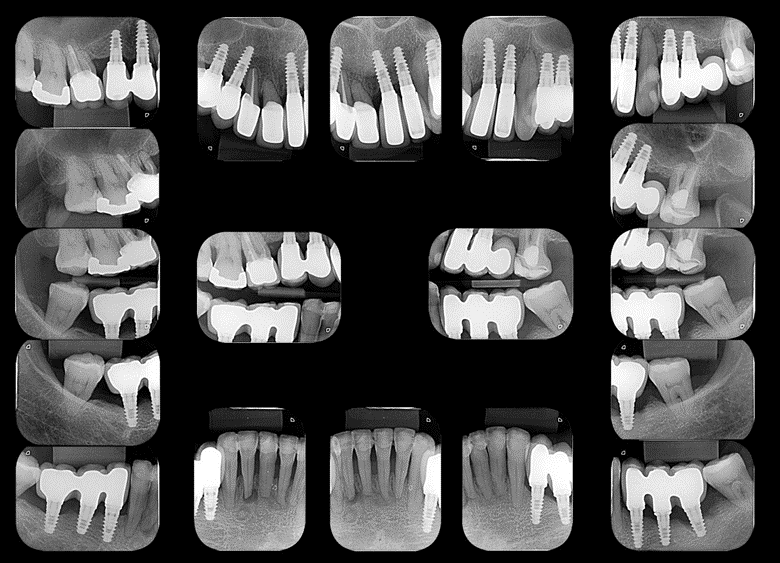

A paciente passou incialmente por tratamento periodontal não cirúrgico previamente à colocação de implantes dentais e reabilitação protética. Para este tratamento, optamos pelo uso de implantes curtos e estreitos em regiões com pouco altura/espessura óssea. Ainda foi utilizada a opção de prótese parcial fixa implantossuportada em cantilever distal, visando evitar procedimentos mais invasivos em região de seio maxilar. Vale ressaltar que embora alguns dentes foram indicados para exodontia, devido a impossibilidade restauradora, a maior parte dos dentes foram passíveis de manutenção. Isto é possível devido a alta previsibilidade da terapia periodontal no que se refere a manutenção de dentes em função, mesmo na presença de significativa perda de inserção.

Após a reabilitação implantossuportada, a paciente foi inserida em terapia periodontal de suporte com retornos regulares visando diagnóstico de infecção periodontal/peri-implantar, prevenção destas condições e tratamento precoce em casos de recidiva da doença periodontal e início de doença peri-implantar. Neste sentido, Herrera et al. (2023) preconizam que a prevenção de doenças peri-implantares deve começar quando os implantes dentários são planejados, colocados cirurgicamente e carregados protéticamente.

Esta abordagem permitiu, em 2018, o diagnóstico de doença peri-implantar no implante colocado na região do dente 36 e, posteriormente ao tratamento desta condição, pode-se observar a estabilidade do nível ósseo nos acompanhamentos radiográficos nos anos de 2021 e 2023.